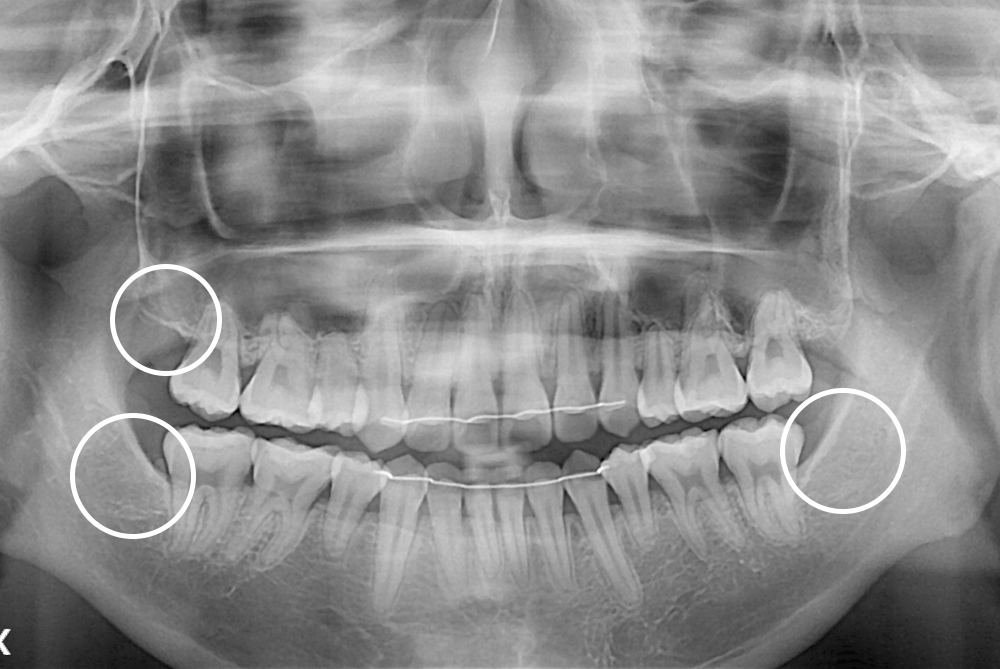

[사랑니] 매복 사랑니 발치

치료전 : 2017-05-09

세종치과는 구강악안면외과학 박사이신 원장님이 발치하는 치과입니다.